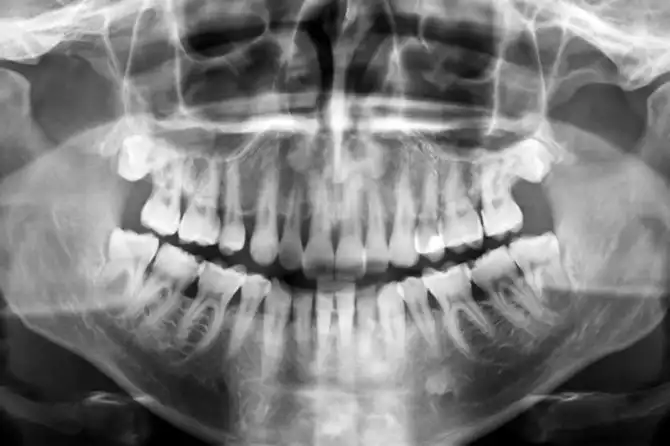

Многие считают, что эффект плацебо вызывает исключительно психологические изменения. Тем не менее есть убедительные доказательства физической реакции тела на прием ложных медикаментов. В 2005 году исследователи из Университета штата Мичиган выполняли сканирование мозга 14 здоровых молодых мужчин. Им в челюстную полость вводили раствор, вызывавший боль. Вскоре пациентам давали плацебо, называя его эффективным обезболивающим. В ходе сканирования исследователи увидели, что области мозга, отвечающие за выработку эндорфинов (гормонов удовольствия), активизировались. Участники также заявляли, что боль утихла, несмотря на то, что никаких объективных предпосылок к этому не было.

После приема плацебо пациенты перестали чувствовать боль в челюсти